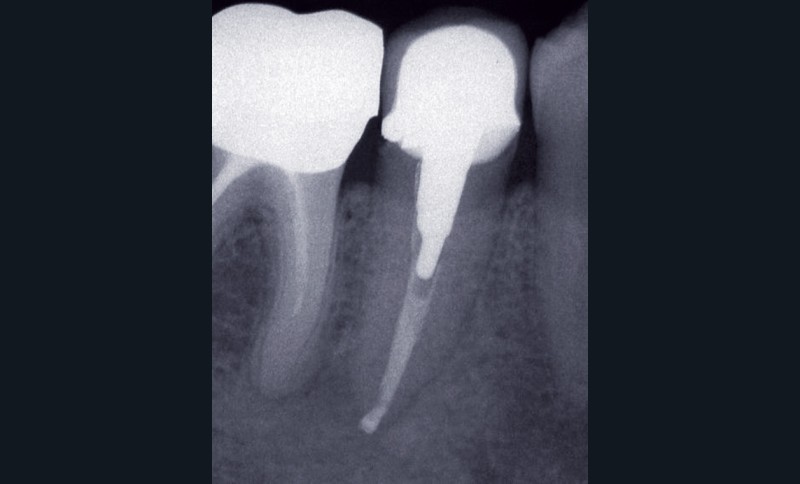

La PAC est fréquemment associée à un silence clinique, expliquant sa découverte généralement fortuite au cours d’une radiographie de contrôle (fig. 2).

Dans certains cas, une douleur à la percussion et éventuellement à la palpation des tissus mous peut être rencontrée. L’image radiographique associée est celle d’une lésion granulomateuse ou d’un kyste. En l’absence de traitement approprié ou d’une diminution des défenses de l’hôte, la lésion peut s’exacerber sous la forme d’un abcès phœnix. La dent devient douloureuse et sensible à la percussion, les tissus mous sont œdematiés et douloureux à la palpation. La présence d’une petite fistule peut parfois être objectivée cliniquement (fig. 3) [13].

La première consiste en la persistance d’une infection intraradiculaire au sein de la zone apicale d’un canal riche en ramifications et en canaux accessoires ou d’un canal oublié (fig. 4) :